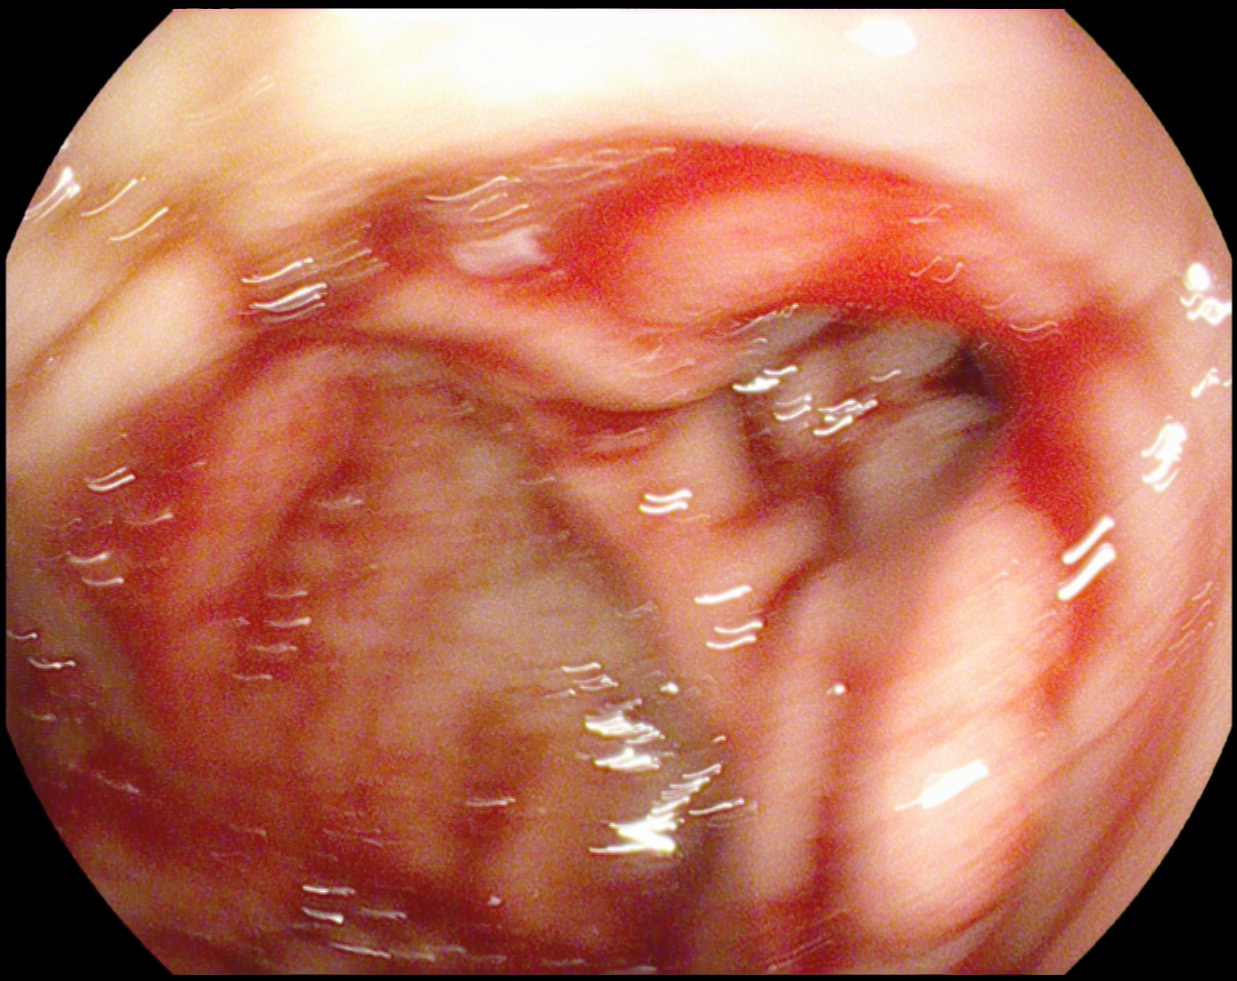

消化内分泌科胃肠镜室于6月1日及6月14日完成2例杜氏病十二指肠降部出血内镜下止血术。

杜氏病是胃粘膜下恒径动脉畸形引起的出血,是一种较少见得引起消化道出血的病因。

其中患者为老年男性,57岁,缘于入院前一天无明显诱因出现反复黑便于5月31日急来我院在消化内科住院,入院血常规血色素为100g/L,给予止血、补液对症治疗无效,出血仍然不止,血常规血色素下降到68 g/L,于6月1日在胃镜室行急诊胃镜,发现患者胃底、胃体、胃窦部大量新鲜出血附着影响观察,继续进镜发现十二指肠球部新鲜出血附着,十二指肠降部见新鲜出血点,呈波动性喷射状,考虑为杜式病引起的十二指肠降部出血,立即给予钛夹钳夹止血,出血停止,给予2单位去白悬浮红细胞,于6月3日复查血常规血色素为78 g/L,于6月6日再次复查血常规血色素为79 g/L,内镜下止血后患者未再呕血及黑便,出血完全止住,准备出院。追问患者病史,患者1年前也因十二指肠出血在承德市中心医院给予钛夹钳夹止血。另1例患者为ICU患者,患者反复呕血、便血15个小时,共输血10U去白悬浮红细胞,1500ml血浆,血色素仍然继续下降,内科保守治疗效果欠佳,仍然出血不止,患者烦躁,生命体征不平稳,在气管插管静脉麻醉下给予内镜下止血治疗后血色素上升,未再呕血,此次内镜下止血为我院完成的杜式病引起出血内镜下止血首例,填补了我院此项技术的空白,同时为患者减少了住院日、减轻治疗花销,同时也避免了转院,给患者带来了福音。